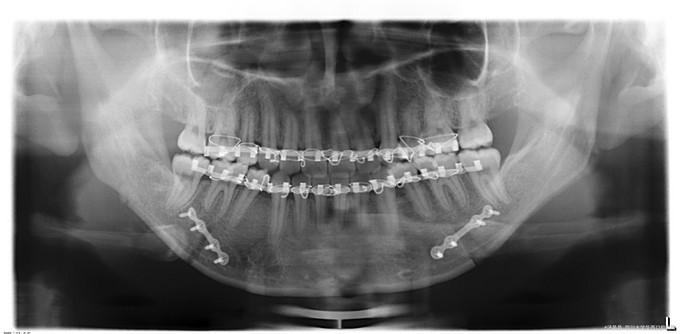

正颌术后复诊,患者因下颌前突一年前在我院正颌外科行BSSRO+双侧下颌骨去骨皮质术+坚固内固定术+牙弓夹板栓扎术,今复诊要求拆钛板

口内检查:上下牙弓关系协调,前牙正常覆合覆盖,后牙正中咬牙合,腔卫生状况良好,全口牙未见明显异常。下颌体双侧扪及钛板,颈部浅表淋巴结未触及。

诊断:正颌术后钛板钛钉存留,在手术室全麻下行“双侧下颌骨钛板钛钉取出术+右下颌骨部磨削术+双侧下颌邻近瓣转移修复术”。手术经过顺利,麻醉满意